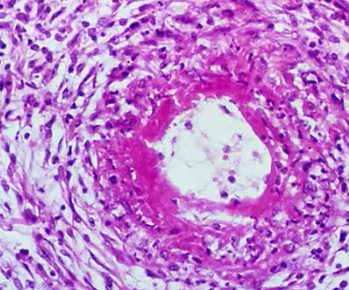

Giant cell arteritis

Fragmentation of elastic lamina associated with giant cell arteritis